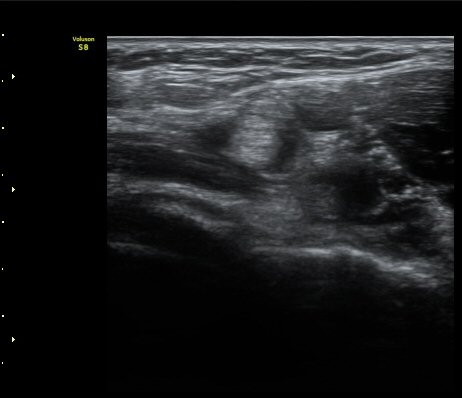

ÆÈ²ÞÄ¡ ¾Õ Ⱦ´Ü¸é°Ë»ç¿¡¼­ À̵ιڱÙÀÌ ÈûÁÙ·Î ÀÌÇàµÇ´Â °ÍÀÌ °üÂûµÈ´Ù(±×¸² 1, 2).

ŽÃËÀÚ¸¦ Á¶±Ý ¸»´ÜÀ¸·Î À̵¿ÇÏ´Ï À̵ιڱ٠ÈûÁÙÀÌ ¶Ñ·ÈÇÏ°Ô °üÂûµÇ°í ÇÔÁÙ ÁÖÀ§¿¡

¼ö¾×Àú·ù°¡  º¸ÀδÙ(±×¸² 3, 4, 5, 6)